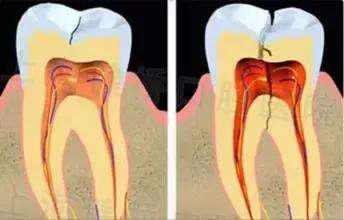

不同深度的牙隐裂

其实牙裂纹深度达到一定程度后,就会出现不同程度的症状。初期可表现为碰到冷热、酸甜等食物后的一过性敏感不适,刺激去除后疼痛即可消失。反复一段时间后,裂纹达到了牙神经的深度,疼痛则逐重,白天什么都不干会疼,夜晚睡觉时也会加重,甚至疼到难以忍受。

浅表的隐裂,医生可适当磨除裂纹,若发现部分尖锐牙尖受力过大,也可适当调改。如果牙齿已经出现冷热刺激痛以及自发痛、夜间痛,那么则需要通过根管治疗加牙冠修复的方式把牙保护起来。